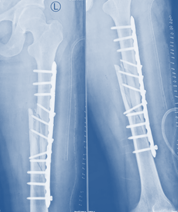

After complete healing and consolidation of regenerated bone, substantiated by radiological evidence Ilizarov apparatus was dispelled 6 month later of installation without removal of plate (Figure 9). He was instructed to incur physiotherapy to recuperate range of motion (ROM) at the knee and hip joint.

Figure 9 Post-operative x-ray after removal of Ilizarov frame without removal of plate.

After 4 months of Ilizarov apparatus removal, there were no pin site wounds, ROM at knee was 0-1200 and normal hip motion. C- reactive protein (CRP) and erythrocyte sedimentation rate (ESR) were done 3 consecutive tests in a week of surgery, the values in normal range and did not increased, also intra-operative bacteriological culture was done to see deep seated infection. There was no evidence of infection. Finally plate was removed. In radiograph there was 150 angulation and 1cm shortening of left lower limb. After 6 months radiograph 130 angulation. One (1) year and four (4) months radiograph after plate removal, there was bone remodeling and 60 angulation with 1 cm shortening of left lower limb found (Figure 10,11).

Figure 10 X-ray after removal of plate and consolidation (1 year & 4 months later).

After clinical and radiological assessment confirmed bony union, after that start dinamization. After complete healing and consolidation of regenerated bone, substantiated by radiological evidence Ilizarov apparatus was dispelled 6 month later of installation without removal of plate (Figure 7). He was instructed to incur physiotherapy to recuperate range of motion (ROM) at the knee and hip joint.

After 4 months of Ilizarov apparatus removal, there were no pin site wounds, ROM at knee was 0-1200 and normal hip motion. C- reactive protein (CRP) and erythrocyte sedimentation rate (ESR) were done 3 consecutive tests in a week of surgery, the values in normal range and did not increased, also intra-operative bacteriological culture was done to see deep seated infection. There was no evidence of infection. Finally plate was removed (Figure 8). In radiograph there was 150 angulation and one (1) cm shortening of left lower limb. After 6 months radiograph 130 angulation. One (1) year and four (4) months after plate removal by bone remodeling there is 60 angulation in radiograph and one (1) cm shortening of left lower limb (Figure 8).